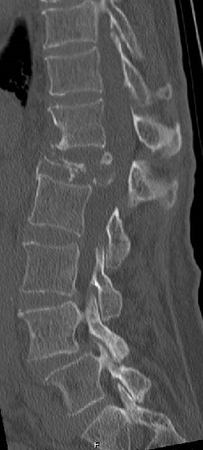

第11胸椎椎体骨折を認めます。骨折部には黒いギャップが存在し、偽関節を呈しています。軽微な後壁損傷も認めます。第1腰椎は椎体骨折後の楔状化変形を認めますが、癒合しています。

骨折部にステントの殻を挿入し、ステント内に骨セメントを充填して治療しました。背中に5mm程度の切開を2か所おいて施します。ステントにより再圧潰が防がれ、また隣接椎体に対する負担も軽減されることが報告されています。